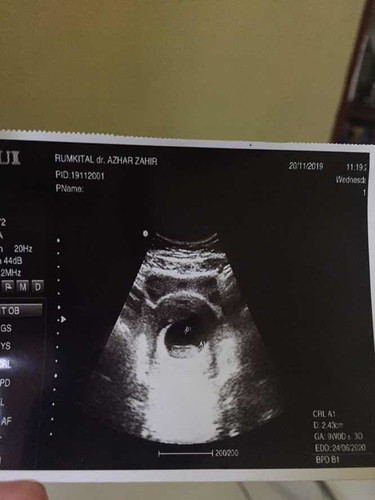

Bulan september 2019 lalu sy senang sekali karena Allah mempercayakan kepada kami, seorang malaikat kecil didalam rahim yg nantinya akan menjadi anak dan cucu pertama untuk kami dan keluarga. Karena kesibukan sy dan suami di Rumah Sakit (kebetulan kami bekerja di 1 tempat kerja), membuat kami menunda untuk USG tp vitamin, makanan, susu, dll tetap sy konsumsi tdk pernah bolong. Sudah mulai masuk uk 9w, setelah wudhu dan akan sholat sy flek coklat. Sy dan suami langsung ke RS rujukan (yg ada Sp.OG nya). Hari itu seperti disambar petir di siang bolong, dokter bilang jantung janin sy tdk berdetak, tidak berkembang, dan disarankan untuk kuret. Tp dokter memberi waktu 2 minggu untuk menunggu apakah janin sy ada perkembangan atau tdk. Sy dan suami langsung blank, tdk bisa berpikir apa2 lagi. Semalaman kami menangis memandangi foto USG janin kami? Besoknya sy tdk kehabisan akal, sy ingin USG di dokter lain. Mencari second opinion. Belum berangkat ke tujuan, sy sudah perdarahan hebat seperti haid. Sy langsung dilarikan ke UGD. Alhasil di kuretlah janin sy? Sempat down, menyalahkan diri sendiri yg terlalu sibuk bekerja. Sampai tdk berani ke makam 2 bulan. Tp kami tdk mau berlama-lama bersedih, kami bangkit. Mencoba ikhlas dan sampai hari ini kami masih promil, makan buat zuriat, kurma, minum asam folat, vit E, dll. Tp belum juga diberi garis 2 bunda.. Doakan ya bunda semoga kami segera diberikan kepercayaan lagi sama Allah. Aminn.. Semoga cerita ini memotivasi bunda2 sekalian yg sedang mengalami apa yg sy alami dulu?